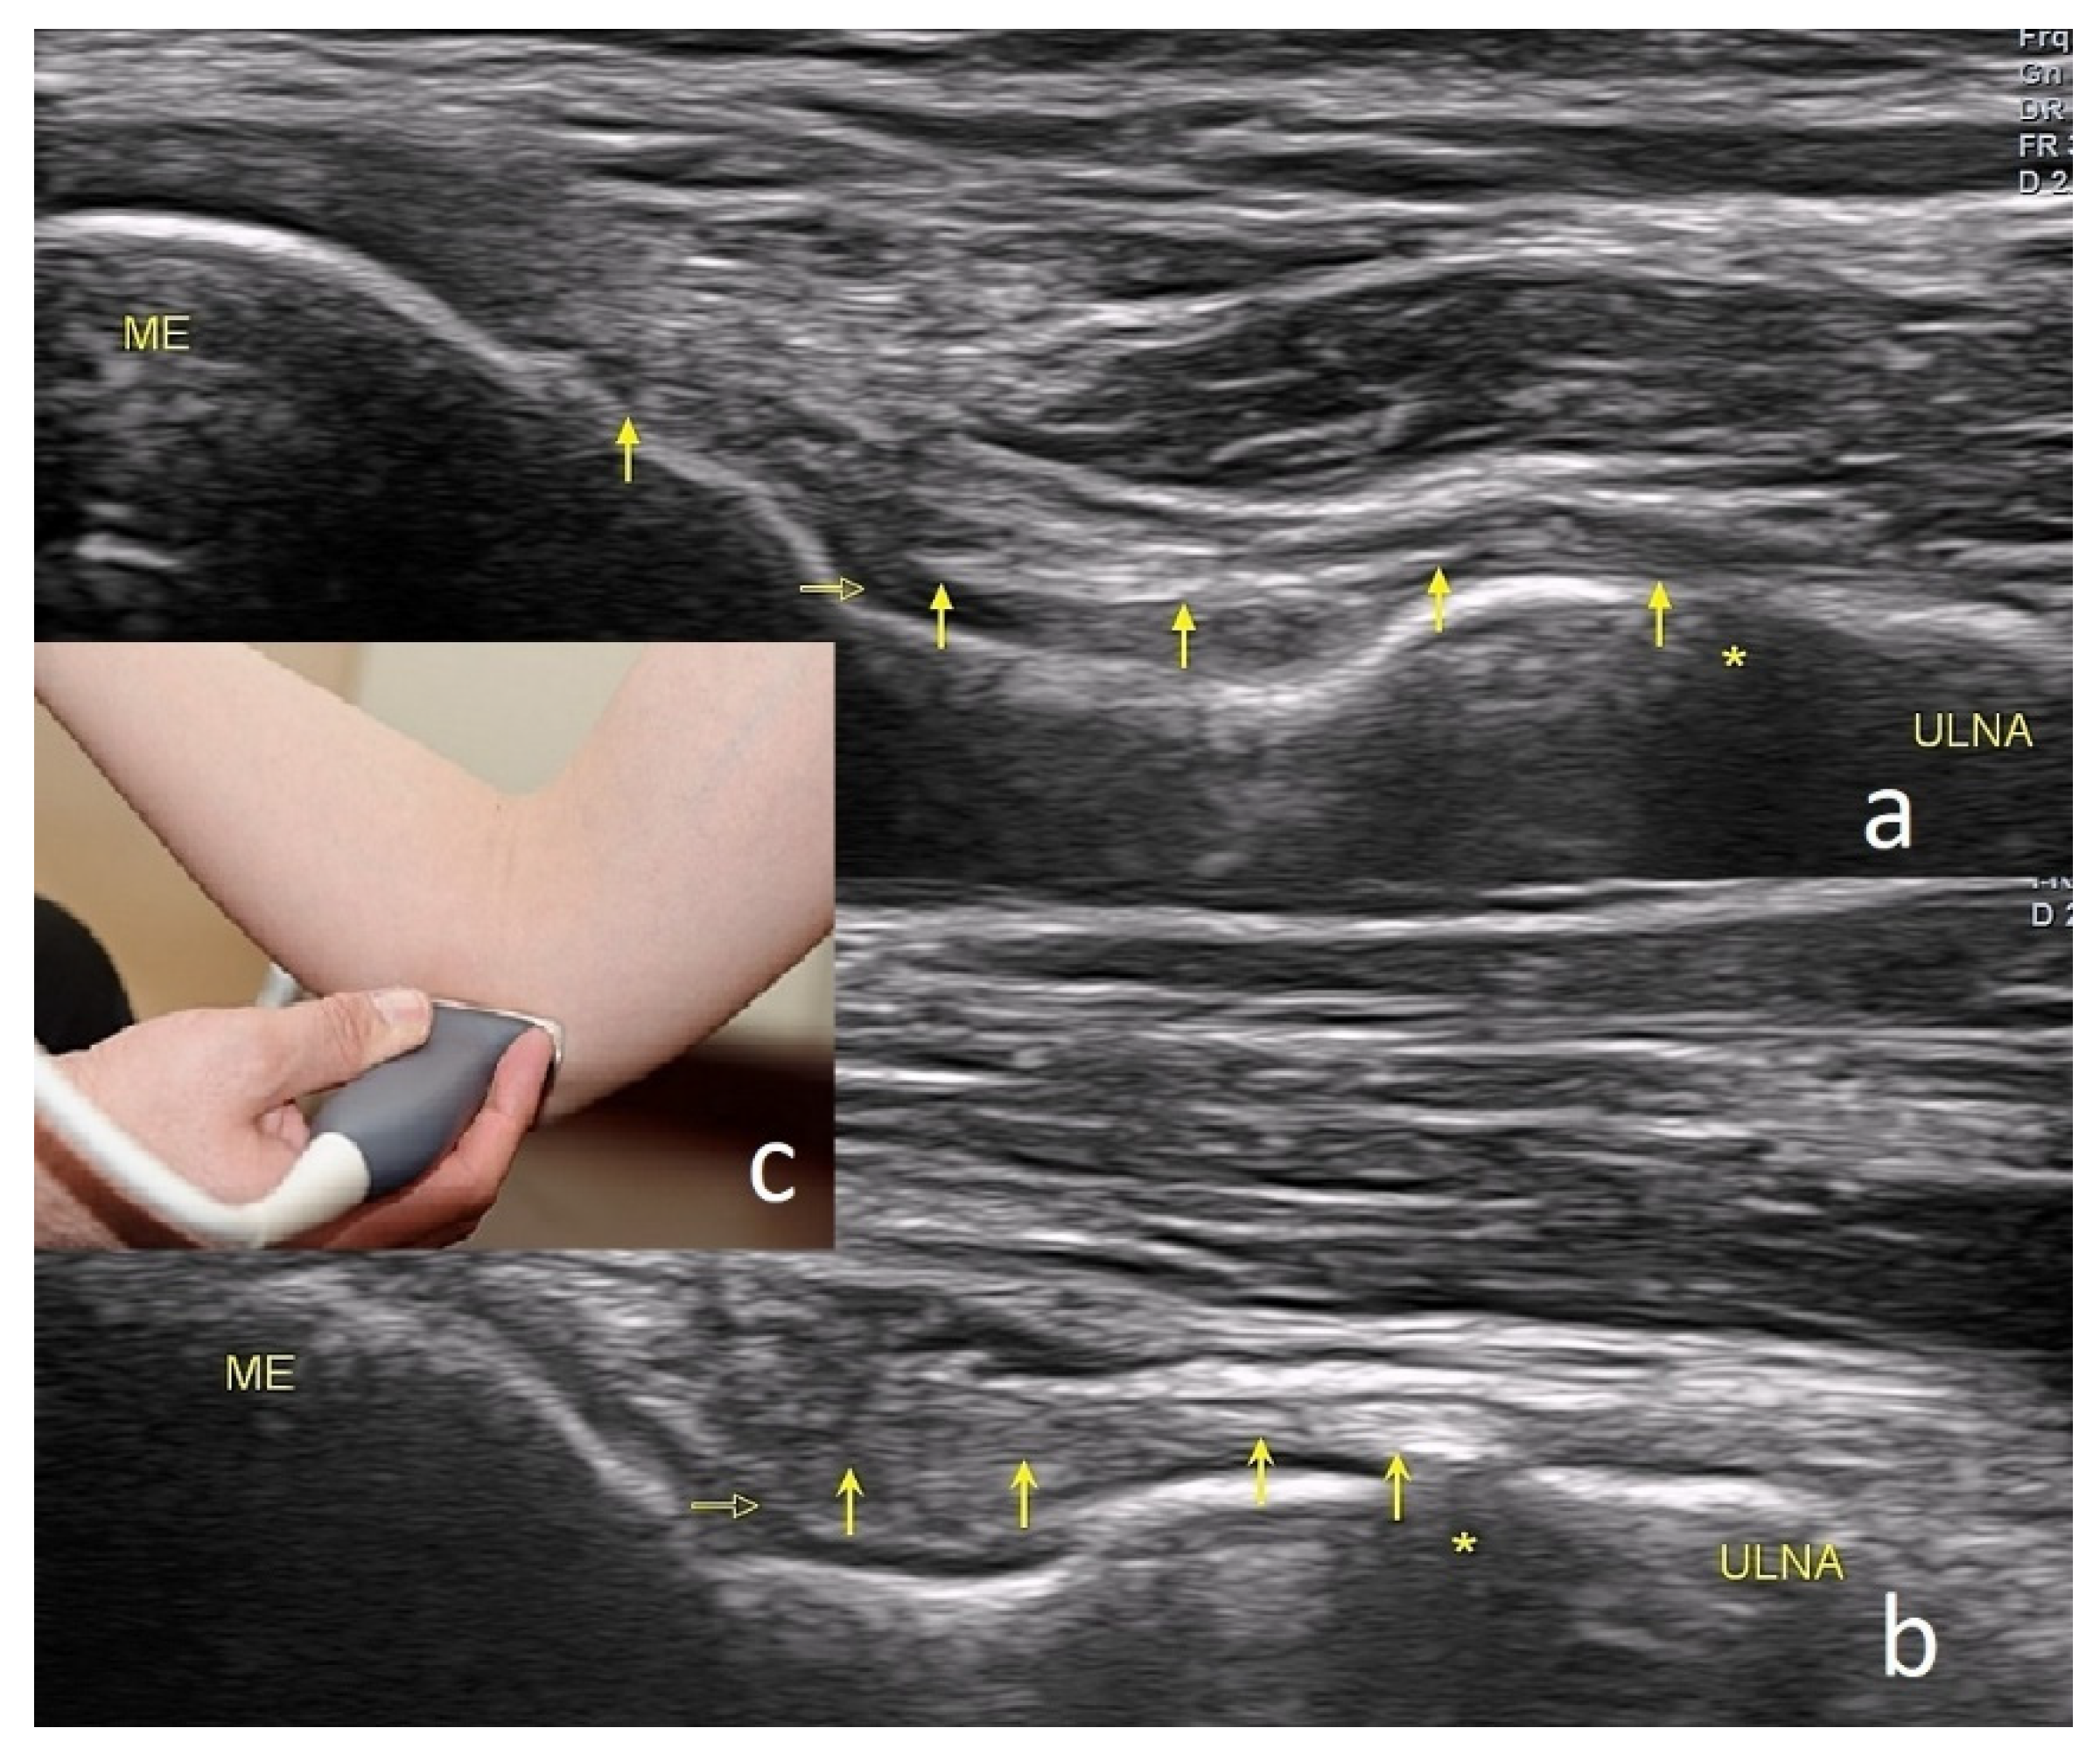

4.1. Cubital Tunnel Syndrome and Ulnar Neuritis

The Technique of Ultrasound Examination of the Medial Portion of the Elbow